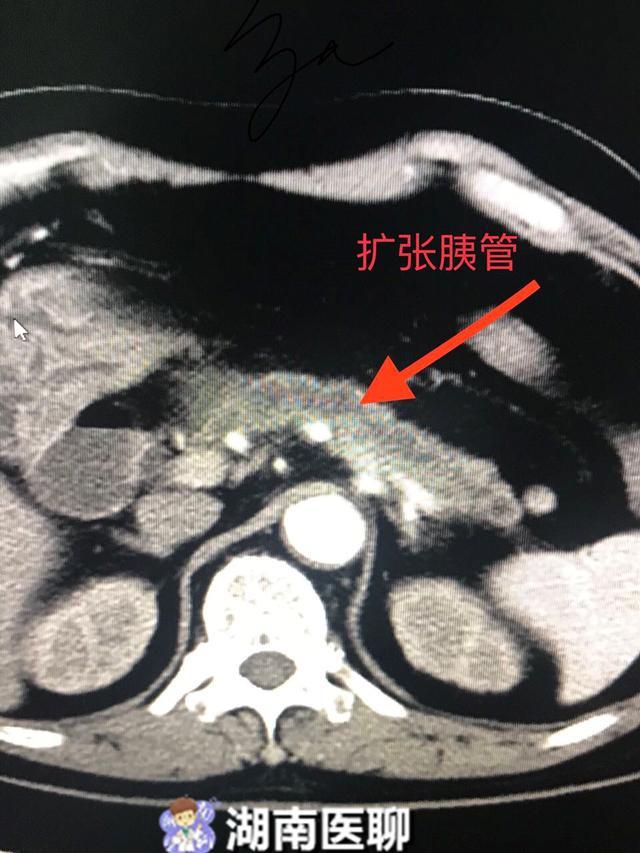

术前增强ct检查提示胆管胰管均扩张

一天后,增强ct报告结果出来了:提示胰管和胆管扩张,壶腹部占位可能.